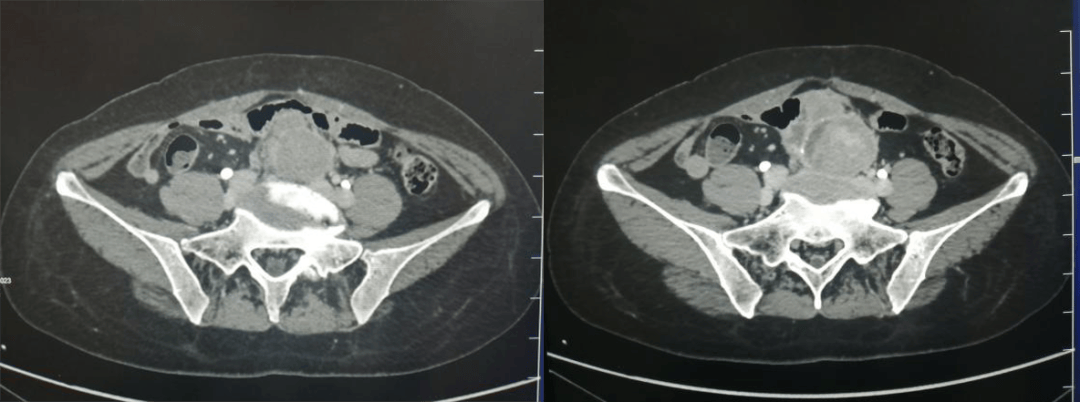

腹膜后异位嗜铬细胞瘤(位于髂血管旁,小肠结构受压向前推移)

宫颈癌,腹膜后淋巴结转移。腹主动脉、下腔静脉及髂血管旁多发肿大淋巴结,T2WI 上呈稍高信号,内部坏死呈明显高信号